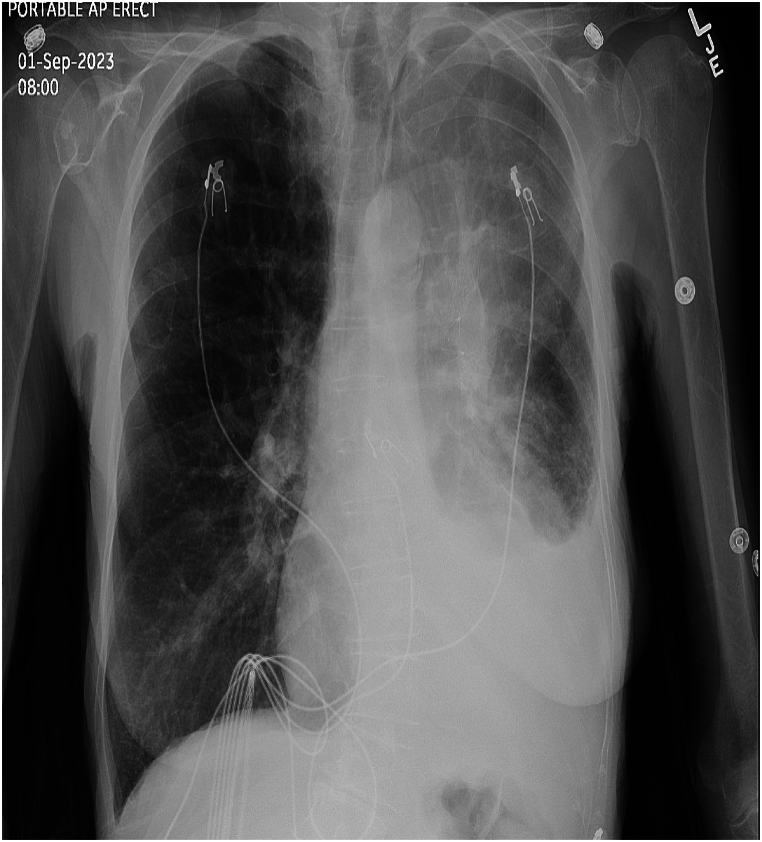

Chronic obstructive lung disease is the third leading cause of death worldwide. It affects the airways and lung parenchyma leading to emphysema. Bronchoscopic lung volume reduction is another strategy that aims to reduce air trapping and hyperinflation, leading to improvement in symptoms and pulmonary function. Several techniques have been employed, one of them is the blocking method using Zephyr or Spiration valves. The use of both valves is approved by the Food and Drug Administration view their established efficacy in improving lung functions, quality of life and survival. Although they have a relatively safe profile, several adverse events have been reported, pneumothorax being the most common and pleural effusion being the least reported. We show herein, a case of 74-year-old female presenting with pleural effusion secondary to bronchoscopic lung volume reduction. Although uncommon, highlighting this potential outcome is crucial.